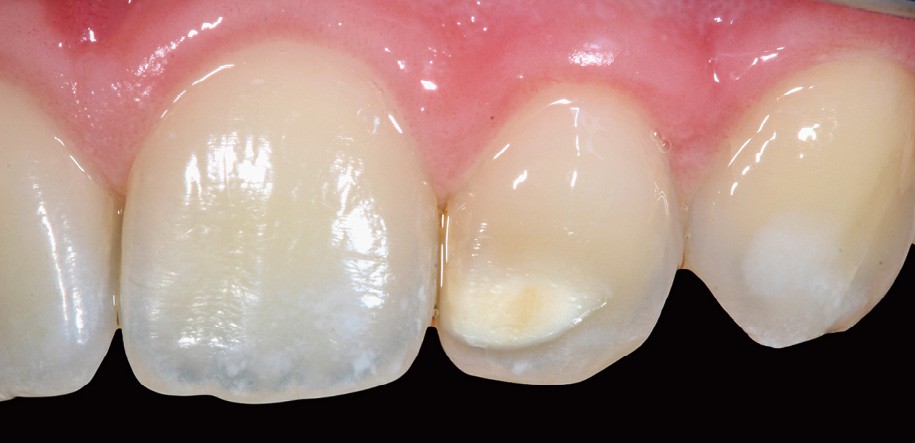

– Traumatismes (fig. 5a, b).